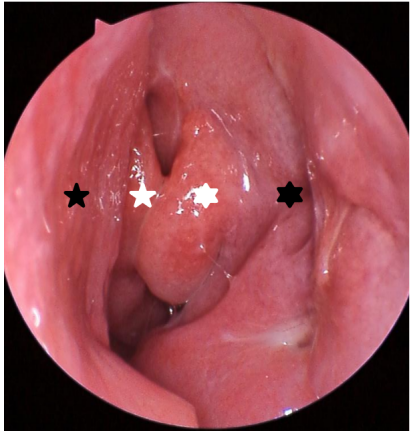

图 5 一例泪道乳头状瘤术后复查鼻内镜所见

Figure 5 Endoscopic picture of a case of lacrimal papilloma after surgery

左侧鼻腔呈术后改变,黏膜愈合好,未见复发征象黑色五角星:正常的鼻中隔;黑色六角形:鼻腔外侧壁呈术后改变,局部凹陷,钩突已经在术中大部去除;白色五角星:中鼻甲;白色六角形:筛泡。The left nasal cavity exhibits postoperative changes with well-healed mucosa and no signs of recurrence. Black five-pointed star: normal nasal septum; black hexagon: the lateral wall of the nasal cavity shows postoperative changes with localized depression, and the uncinate process has been largely removed during surgery; white five-pointed star: middle turbinate; white hexagon: ethmoid bulla.